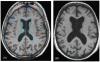

Methods and findings: Single-center, randomized, double-blind controlled trial of high-dose folic acid, vitamins B(6) and B(12) in 271 individuals (of 646 screened) over 70 y old with mild cognitive impairment. A subset (187) volunteered to have cranial MRI scans at the start and finish of the study. Participants were randomly assigned to two groups of equal size, one treated with folic acid (0.8 mg/d), vitamin B(12) (0.5 mg/d) and vitamin B(6) (20 mg/d), the other with placebo; treatment was for 24 months. The main outcome measure was the change in the rate of atrophy of the whole brain assessed by serial volumetric MRI scans.

Results: A total of 168 participants (85 in active treatment group; 83 receiving placebo) completed the MRI section of the trial. The mean rate of brain atrophy per year was 0.76% [95% CI, 0.63-0.90] in the active treatment group and 1.08% [0.94-1.22] in the placebo group (P = 0.001). The treatment response was related to baseline homocysteine levels: the rate of atrophy in participants with homocysteine >13 µmol/L was 53% lower in the active treatment group (P = 0.001). A greater rate of atrophy was associated with a lower final cognitive test scores. There was no difference in serious adverse events according to treatment category.

Conclusions and significance: The accelerated rate of brain atrophy in elderly with mild cognitive impairment can be slowed by treatment with homocysteine-lowering B vitamins. Sixteen percent of those over 70 y old have mild cognitive impairment and half of these develop Alzheimer's disease. Since accelerated brain atrophy is a characteristic of subjects with mild cognitive impairment who convert to Alzheimer's disease, trials are needed to see if the same treatment will delay the development of Alzheimer's disease.